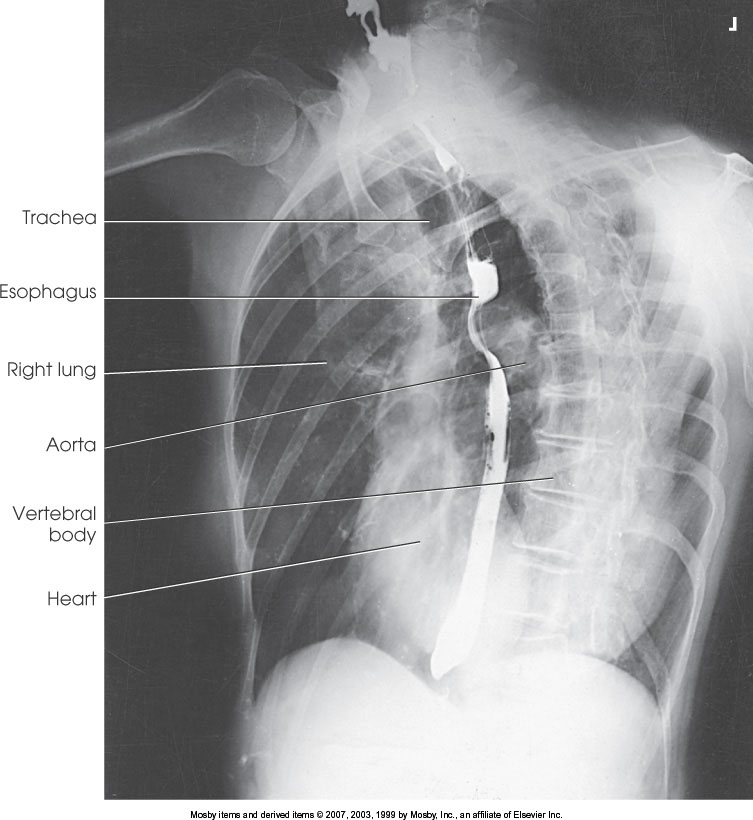

What position is demonstrated?

LAO Chest